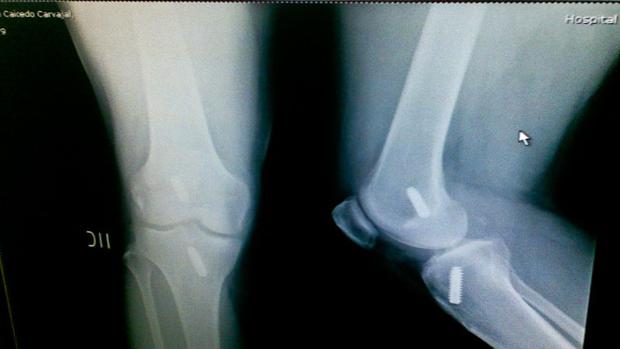

La gota es una enfermedad reumática dolorosa que causa inflamación en las articulaciones debido a los depósitos de urato (sal de ácido úrico) en los tejidos, tendones y ligamentos. Se trata de una patología muy frecuente, ya que su prevalencia alcanza el 2,4% de la población adulta en España, lo que supone más de 800.000 pacientes, según el estudio EPISER 2016 de la Sociedad Española de Reumatología (SER) . Además, se estima que 1 de cada 3 afectados está sin diagnosticar, ya que «a veces los primeros síntomas pueden ser banales o inexistentes, y hay casos atípicos en mujeres o en ancianos, que pasan desapercibidos», según explica el Dr. Enrique Calvo, reumatólogo del Hospital Universitario Infanta Leonor (Madrid). Existen numerosos pacientes seguidos en otras especialidades diferentes a la Reumatología con enfermedad renal crónica, psoriasis, hipertensión arterial o cardiopatía isquémica que además tienen hiperuricemia y gota sin diagnosticar. En España, se estima que un 7% de los varones adultos tienen altos niveles de ácido úrico en sangre (hiperuricemia). «Si además se tiene en cuenta que habría que incluir como gota también a aquellos pacientes que tienen cálculos renales de ácido úrico o tofos (acúmulos tisulares de ácido úrico bajo la piel en zonas como los codos) y no han consultado al médico nunca por ese motivo, así como a las personas que tienen depósitos de cristales de ácido úrico en las articulaciones o en alguna otra localización sin padecer ningún síntoma (gota subclínica), es muy probable que la cifra sea más alta, pudiendo superar el millón de españoles con esta enfermedad», advierte el Dr. Calvo. La técnica para lograr el diagnóstico definitivo sigue siendo a través de un microscopio óptico, aunque la ecografía también ha demostrado su eficacia y va ganando terreno El patrón oro para alcanzar el diagnóstico definitivo de la gota sigue siendo el examen con microscopio óptico de luz polarizada, que permite detectar a los causantes de la enfermedad, los cristales de ácido úrico, en el líquido de articulaciones inflamadas o en material extraído de tofos, con una alta especificidad. Asimismo, explica el Dr. Calvo, «la obtención de líquido articular de un paciente con inflamación de una rodilla, un tobillo, un codo, una muñeca o el dedo gordo del pie puede permitir, realizar un estudio complementario microbiológico, bioquímico y de contaje celular. Ocasionalmente puede existir presencia de dos tipos de cristales en una articulación (pirofosfato de calcio y urato), o detectarse una infección bacteriana añadida a la gota». Sin embargo, -añade el reumatólogo- en los últimos años diferentes técnicas de imagen como el DECT (tomografía computarizada de doble energía) y, sobre todo, la ecografía (inocua y más accesible) se han posicionado como útiles herramientas que mejoran la precisión del diagnóstico de la gota, incorporándose también a los nuevos criterios de clasificación internacionales empleados en los estudios de esta enfermedad. Además, la ecografía permite cuantificar el número de articulaciones con inflamación y/o depósito cristalino, y también sirve de ayuda a la hora de guiar al médico en infiltraciones articulares y extracción de material para estudio mediante punción. Es por ello que está cada vez más presente en las consultas de Reumatología y otras especialidades como Atención Primaria o Traumatología. Síntomas de alerta de la gota Los síntomas más característicos de articulaciones con gota son 4: dolor (puede ser muy intenso, incluso con mínimos roces, produciendo a veces cojera al paciente), hinchazón, calor y enrojecimiento. En opinión del especialista, «suele ser típico encontrar valores elevados de ácido úrico en algunas analíticas del paciente, pero no tiene por qué estar alta la uricemia en el momento del ataque, ni siempre igual de alta. Además, las concentraciones en sangre pueden variar y no son infrecuentes los casos de gota con niveles aparentemente bajos de úrico». Las concentraciones en sangre pueden variar y no son infrecuentes los casos de gota con niveles aparentemente bajos de úrico «Se podría decir que cualquier paciente con inflamación articular recurrente o resistente al tratamiento instaurado en Urgencias o Atención Primaria debería ser derivado a consultas de Reumatología para su valoración. También pueden ser derivados al reumatólogo aquellos casos en los que existan dificultades en el manejo (por comorbilidades como enfermedad renal o cardiovascular) o ante dudas en el diagnóstico clínico en los pacientes con altos niveles de ácido úrico en sangre y/o con antecedentes de gota en familia, ya que, aunque no tengan síntomas típicos, pueden padecer formas subclínicas o poco sintomáticas de la enfermedad», precisa el Dr. Calvo.Fuente Salud https://ift.tt/2meUaPZ